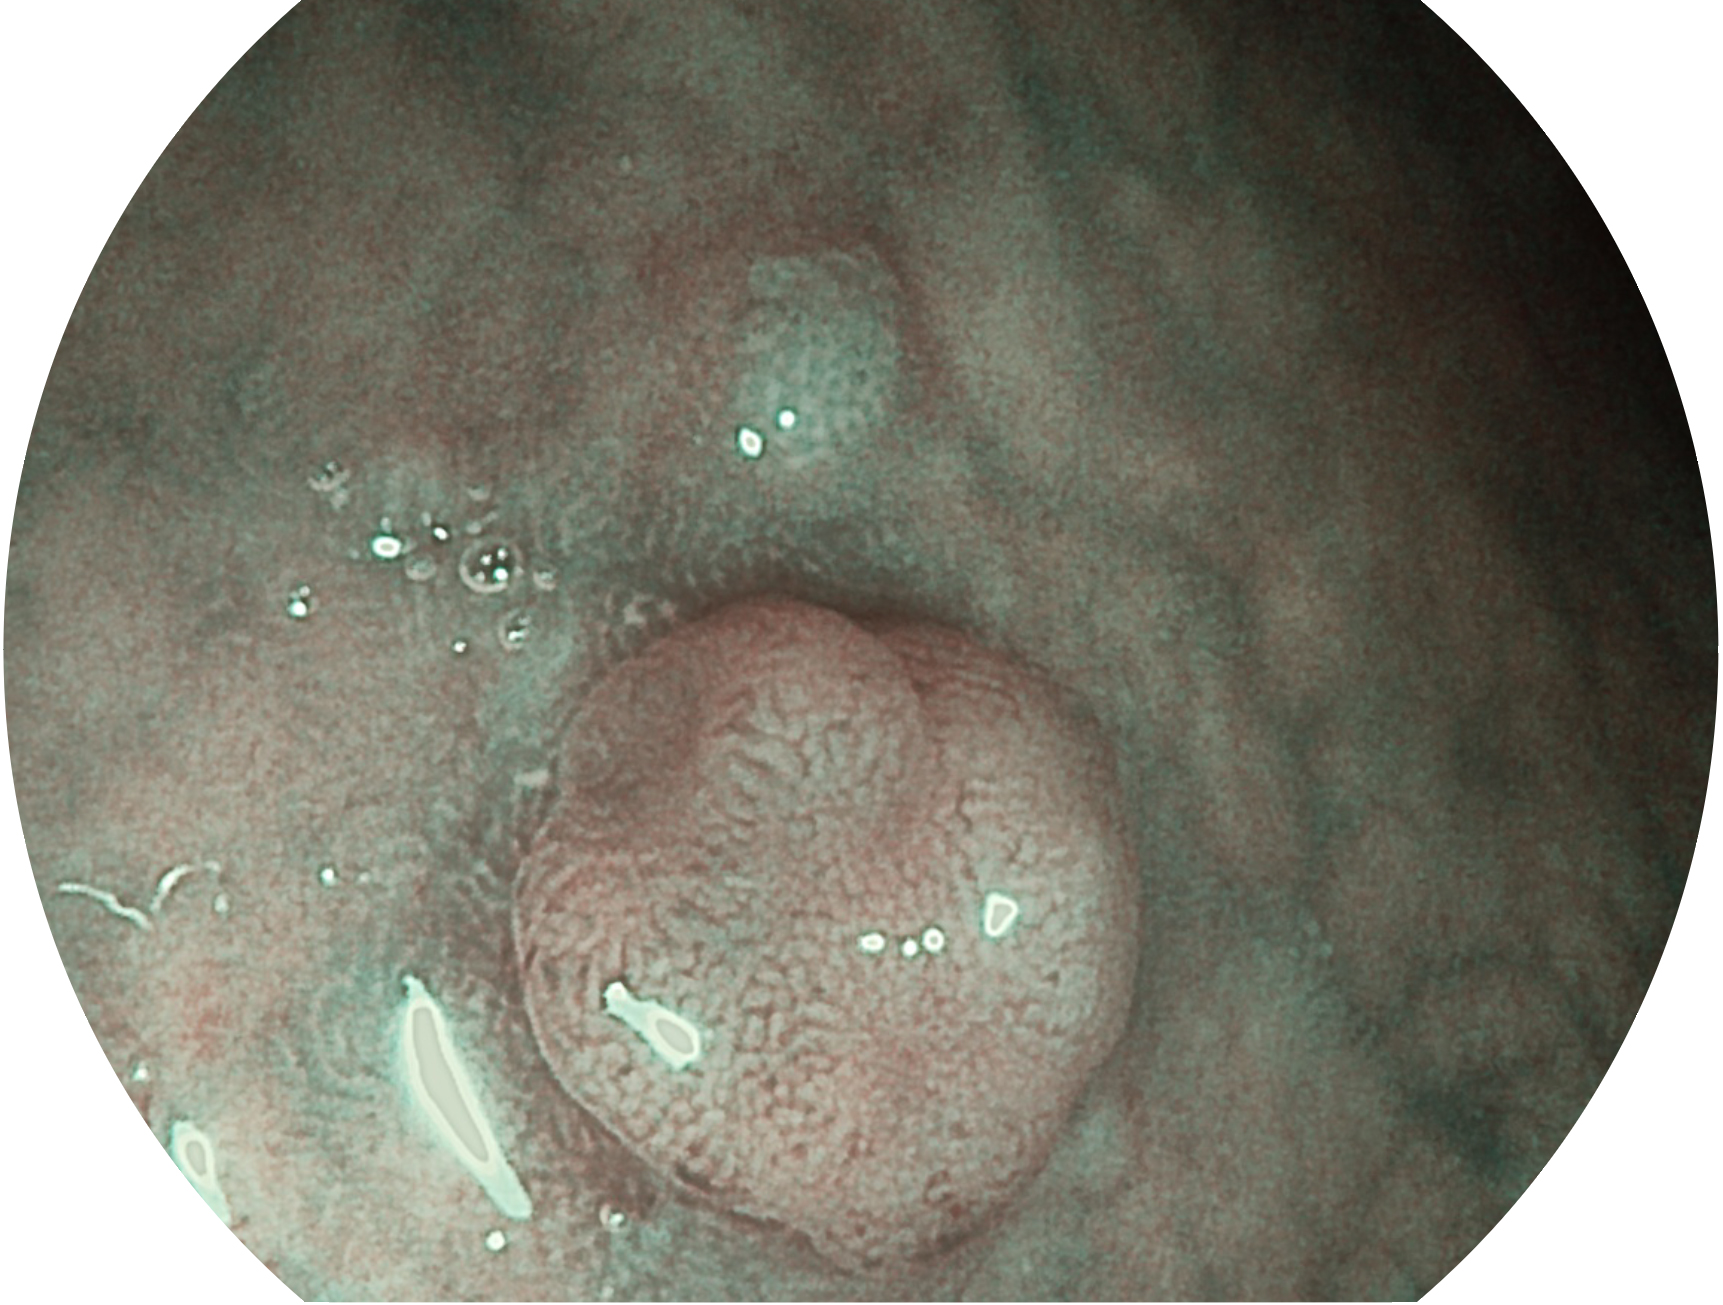

百老汇电子游戏官网新开发的内镜染色技术,主要是基于多波长LED 光源的开发,VLS-55Q 四波长LED 光源是由四个不同颜色的LED光按照相应照明模式所规定的特定发光比例进行合束后形成,合束后形成的照明光的光谱由红光、绿光、蓝光及蓝紫光这四个不同的波段范围构成。具有更高光谱自由度,通过光谱比例的控制,实现了聚谱成像技术,英文全称为“Spectral Focused Imaging, SFI”,缩写为“SFI”和光电复合染色成像技术,英文全称为“Versatile Intelligent Staining Technology, VIST”,缩写为“VIST”。